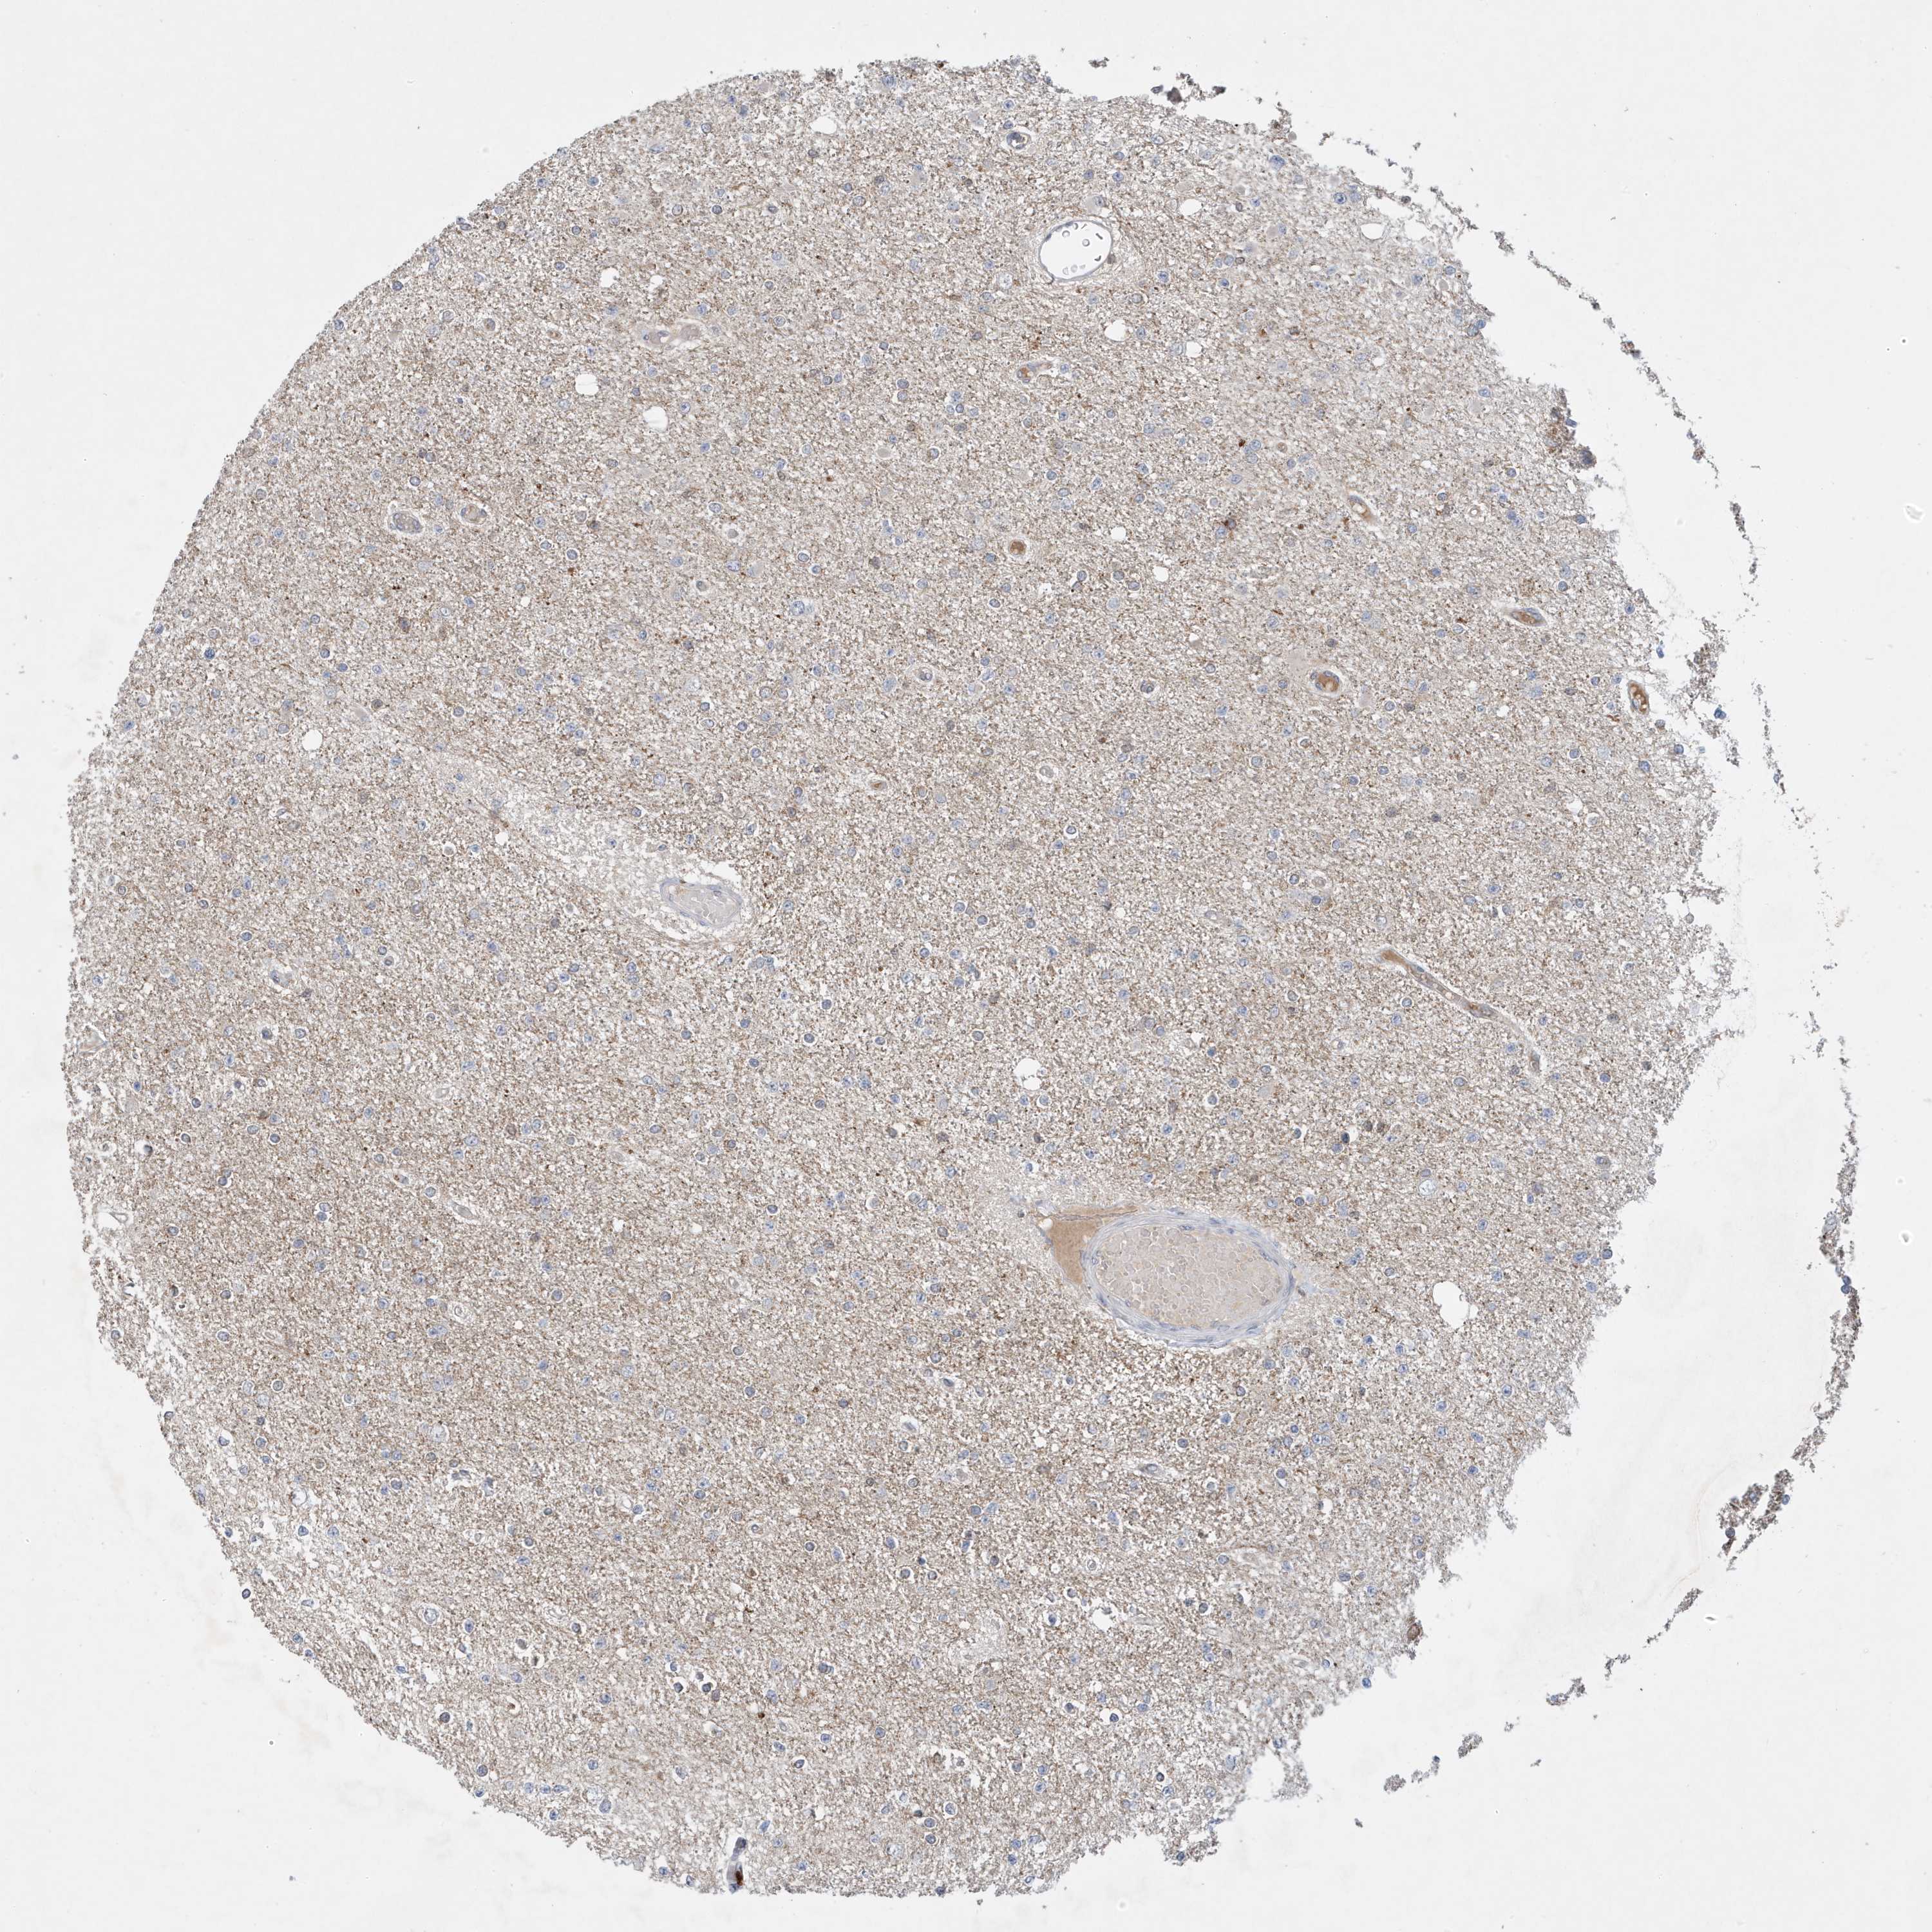

GLIOMA - Protein expressioni

A mouse-over function shows sample information and annotation data. Click on an image to view it in a full screen mode. Samples can be filtered based on level of antibody staining by selecting one or several of the following categories: high, medium, low and not detected. The assay and annotation is described here.

Note that samples used for immunohistochemistry by the Human Protein Atlas do not correspond to samples in the TCGA dataset.

Antibody stainingi

Antibody staining in the annotated cell types in the current human tissue is reported as not detected, low, medium, or high, based on conventional immunohistochemistry profiling in selected tissues. This score is based on the combination of the staining intensity and fraction of stained cells.

Each image is clickable and will lead to virtual microscopy that enables deeper exploration of all samples and also displays staining intensity scores, fraction scores and subcellular localization as well as patient and tissue information for each sample.

Antibody HPA036181

Staining

High

Medium

Low

Not detected

Intensity

Strong

Moderate

Weak

Negative

Quantity

>75%

75%-25%

<25%

None

Location

Nuclear

Cytoplasmic/membranous

Cytoplasmic/membranous,nuclear

Glioma, malignant, High grade

Glioma, malignant, Low grade

Glioblastoma, NOS